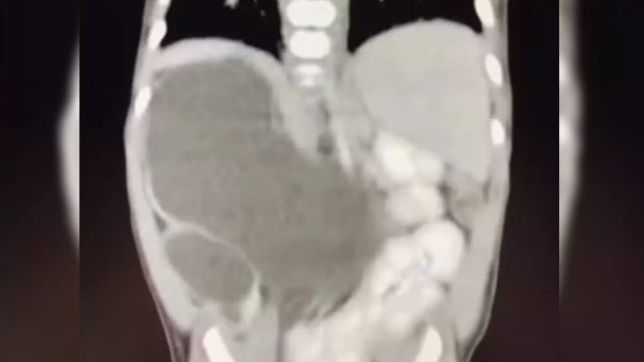

Incluída nos casos raríssimos da medicina, uma menina nasceu com quatro rins. Hoje com 1 ano e 1 mês, a pequena Isis Eloah Ferreira Alves está entre os cerca de 100 casos da medicina documentados na literatura mundial. O caso, publicado pelo G1, é é conhecido na medicina como “rins supranumerários” e demanda acompanhamento.

Aos 5 meses, quando houve a necessidade de Isis passar por uma cirurgia, os médicos confirmaram que ela tinha nascido com quatro rins. Como Formosa fica a cerca de 80 quilômetros do Distrito Federal, a menina hoje é tratada no Hospital da Criança de Brasília (HCB).

Os médicos da unidade explicam que a quantidade superior de rins se dá devido a uma má formação ainda na getação. Ainda não existe explicação porque se desenvolve mais de um rim em cada lado.

O médico que a acompanha, Hélio Buson, afirmou ao G1 que ter vários rins não apresenta anormalidade para o corpo. Assim, os órgãos podem passar despercebidos ao longo da vida e só serem notados na vida adulta. É necessário que haja acompanhamento.